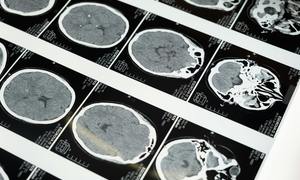

Mamy bardzo dobre metody obserwacji przy użyciu technik obrazowych, takich jak rezonans magnetyczny. Jeśli guz po operacji szybko rośnie, wtedy chory powinien być leczony przy użyciu radio- i chemioterapii. Nowy lek, o którym mówimy, daje chorym po całkowitym wycięciu guza i bez wyraźnej progresji po operacji dodatkowo długi czas do progresji choroby.